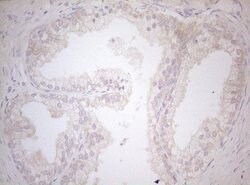

MXD4 Monoclonal Antibody (OTI7F7), TrueMAB™, OriGene

| Immunohistochemistry (Paraffin), Western Blot | |